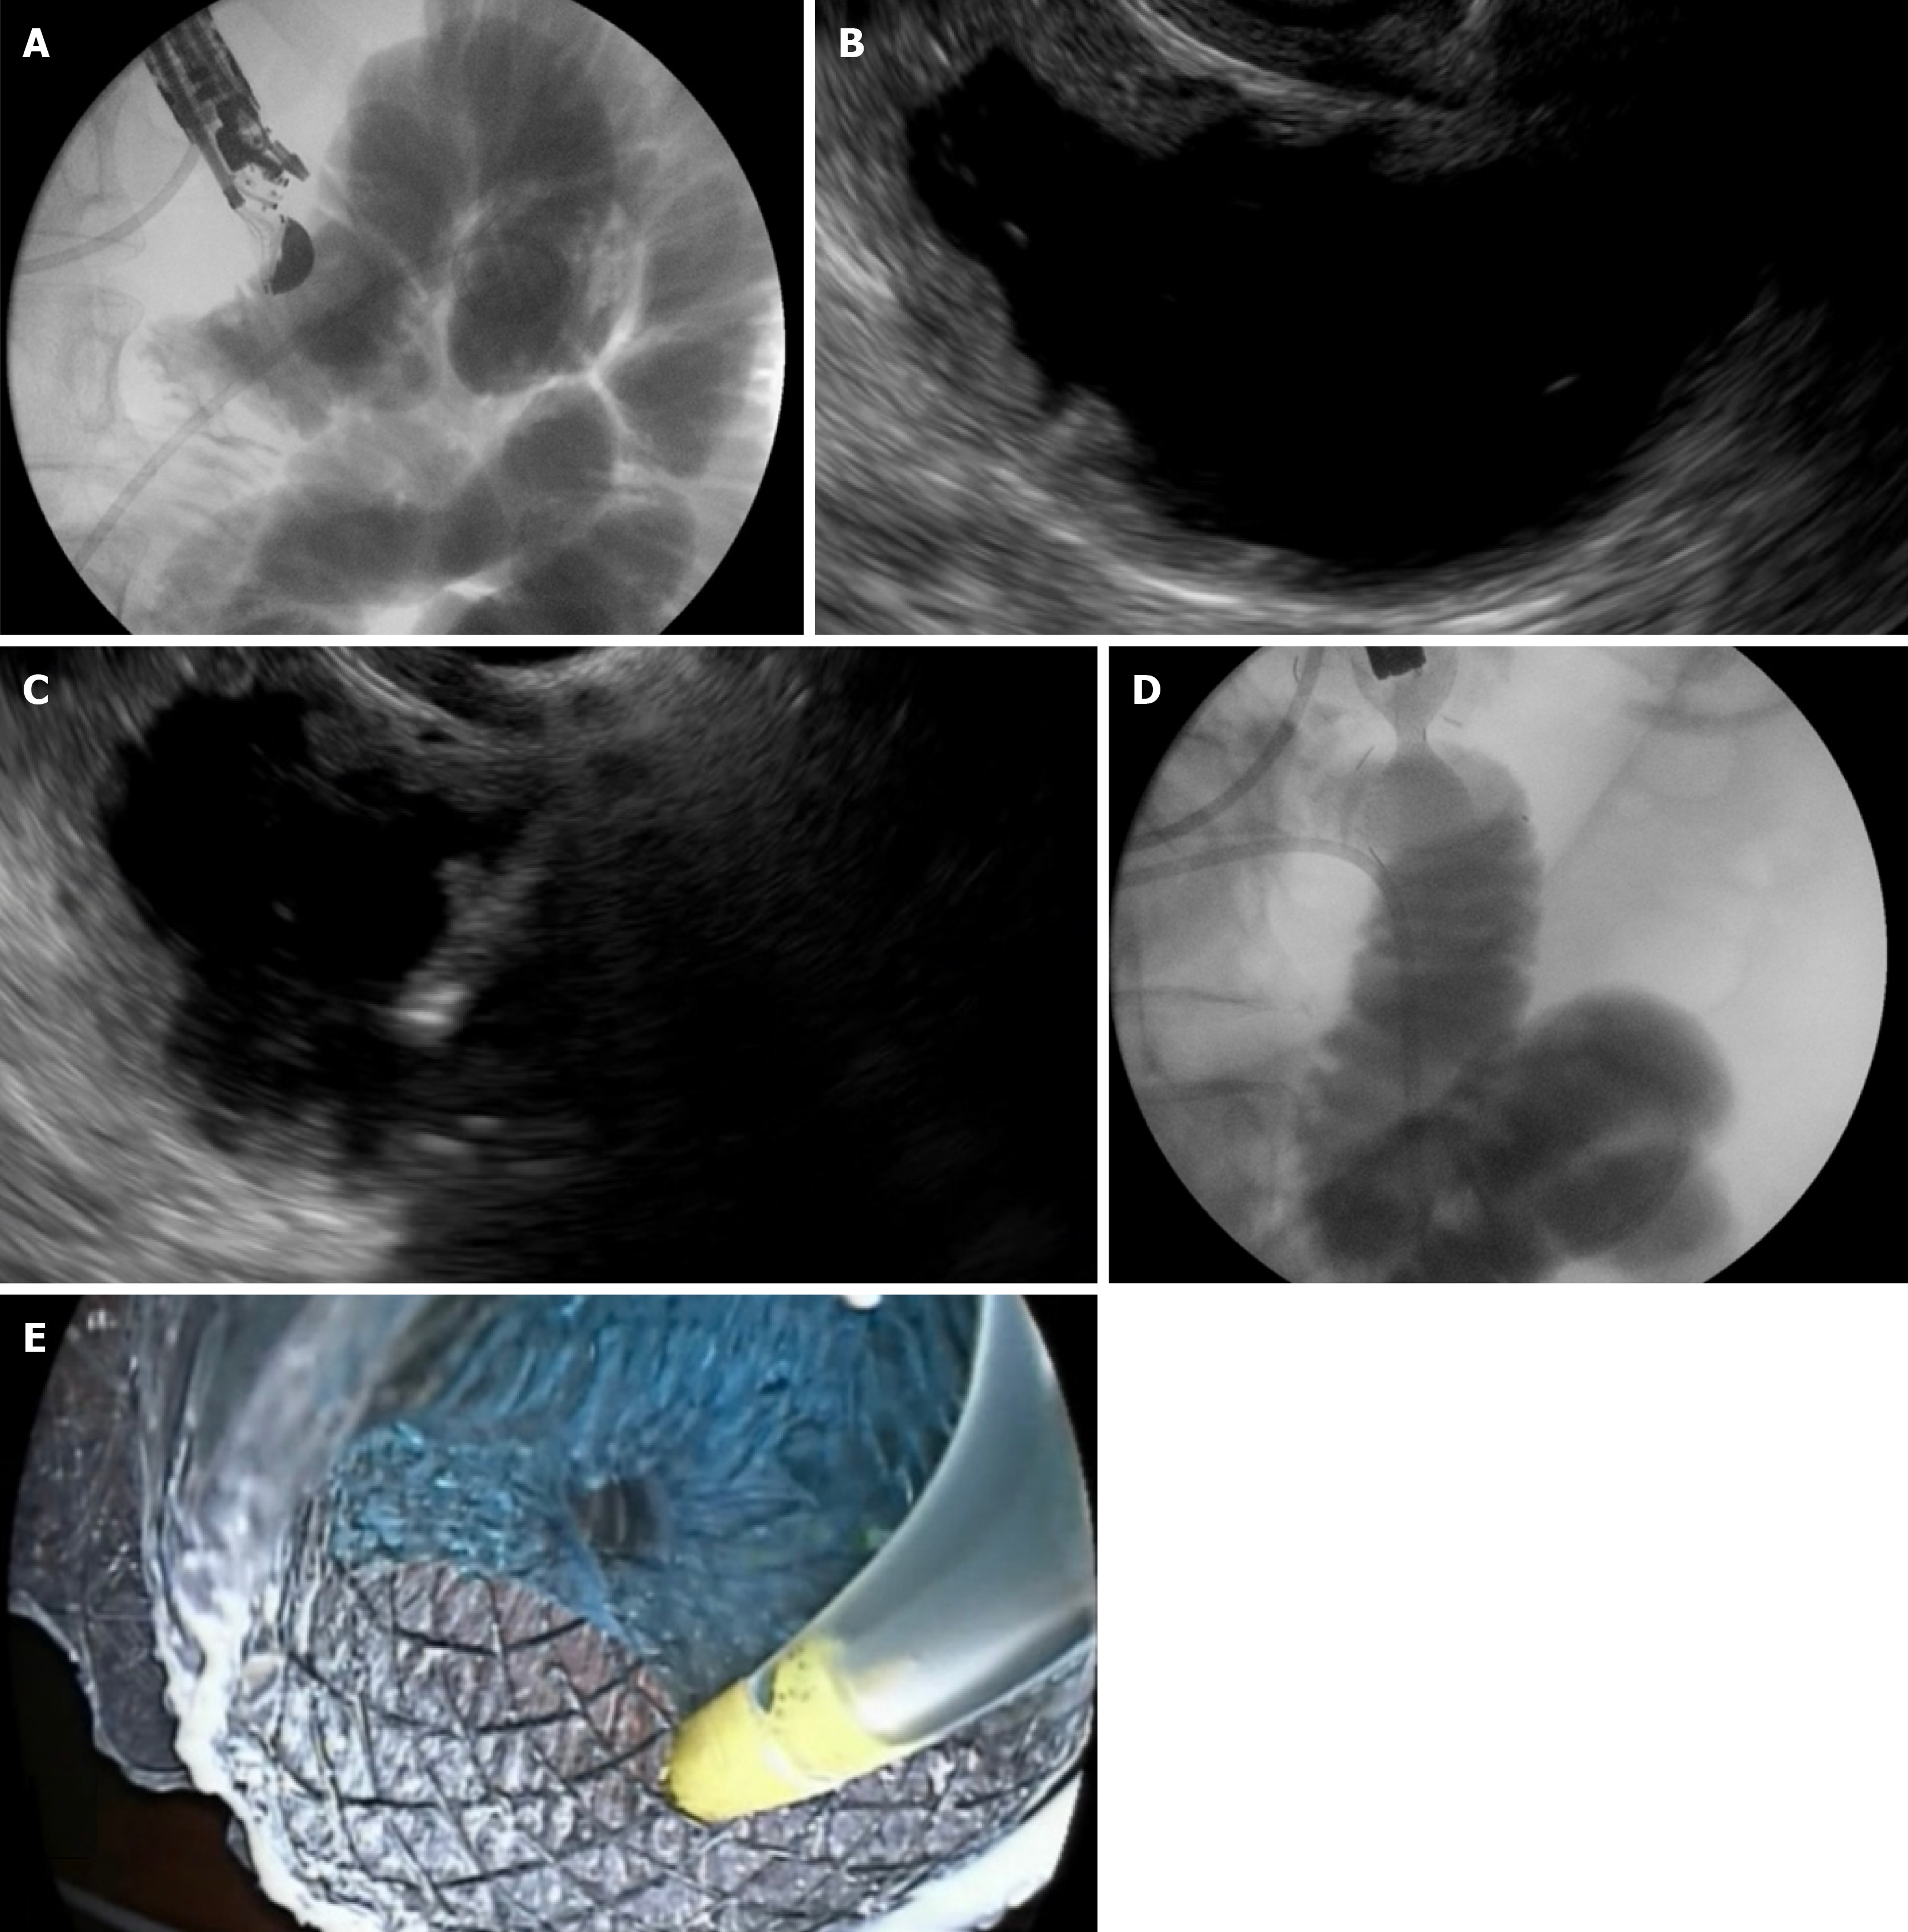

Figure 2 Step-by-step visualization of endoscopic ultrasound-guided gastroenterostomy procedure.

A: Fluoroscopic view showing a 7Fr nasobiliary catheter placed into the jejunum over a guidewire; B: Echoendoscopic view displaying the duodenum and jejunum distended with contrast material and methylene blue before direct puncture; C: Real-time puncture of the stomach and jejunal wall using the freehand technique under endoscopic ultrasound guidance; D: Fluoroscopic confirmation of successful stent deployment; E: Endoscopic confirmation ensuring correct positioning and lumen patency of the deployed stent.